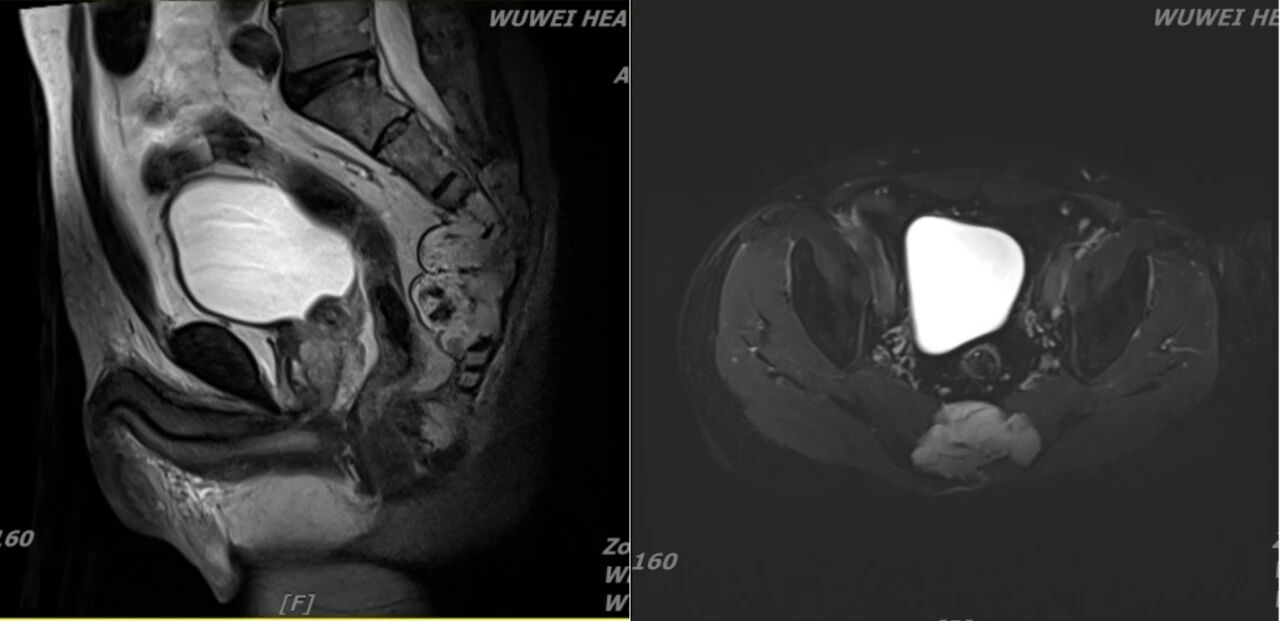

三、患者男,58岁,骶尾部脊索瘤,2022年5月25日行重离子治疗。

治疗前2022年4月25日 治疗后2024年6月4日